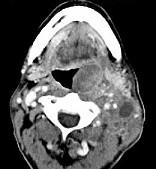

问题 男,67岁,口咽部异物感约8个月,伴口咽部疼痛,患者无明显发热.如图所示最可能的诊断为()

选项 A.扁桃体结核伴淋巴结转移 B.扁桃体脓肿伴淋巴结转移 C.扁桃体癌伴淋巴结转移 D.扁桃体淋巴瘤 E.下咽癌伴淋巴结转移

答案 C